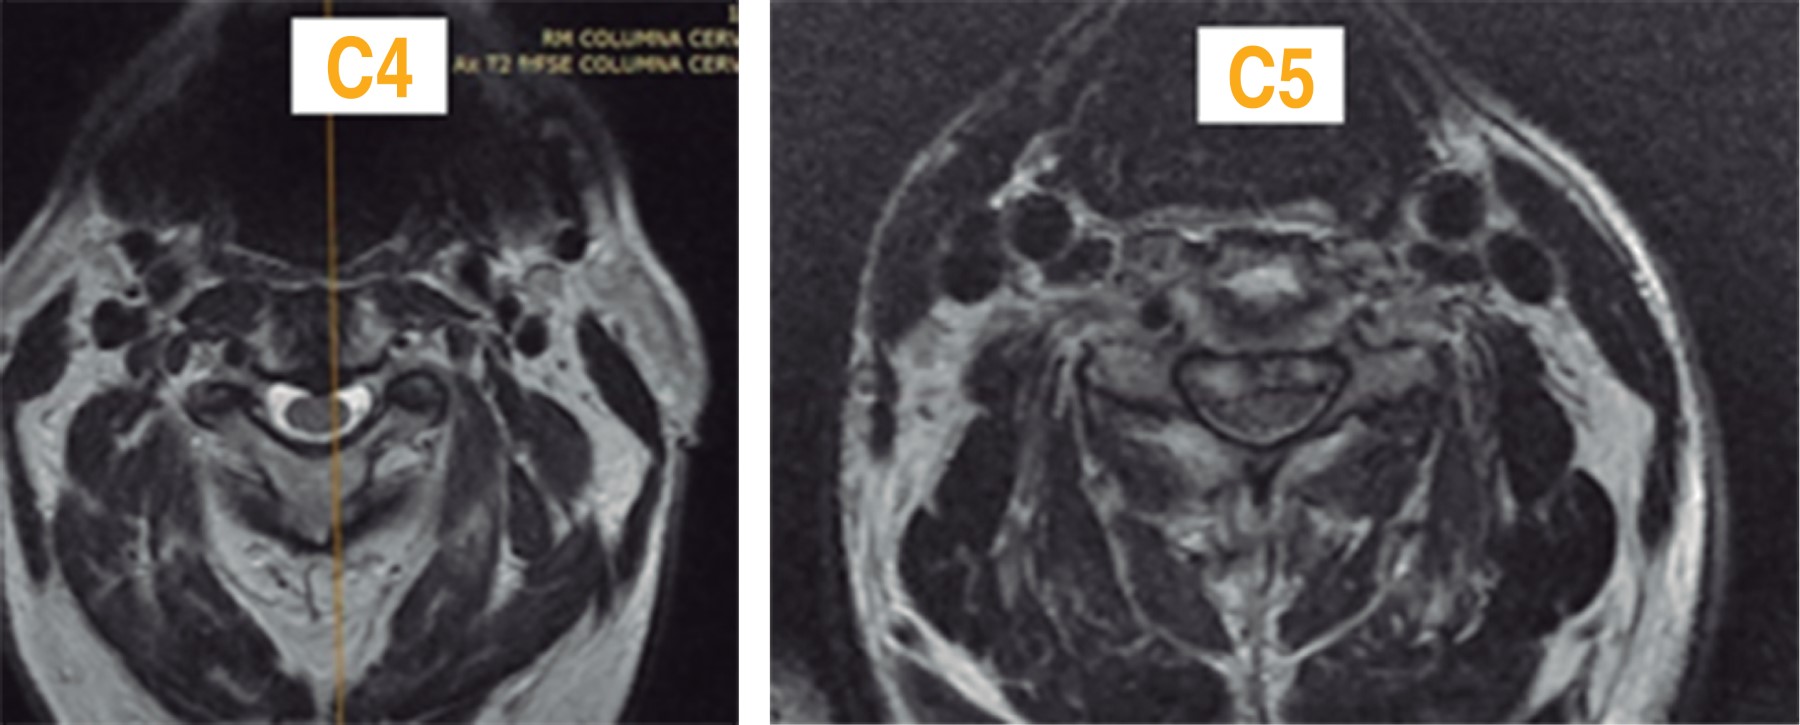

Figure 3

Figure 4